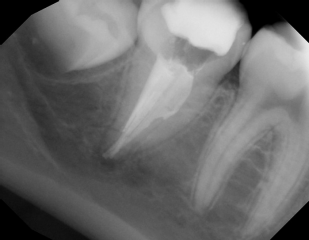

#3 S-RCT

Dx: Previously Treated with SAP